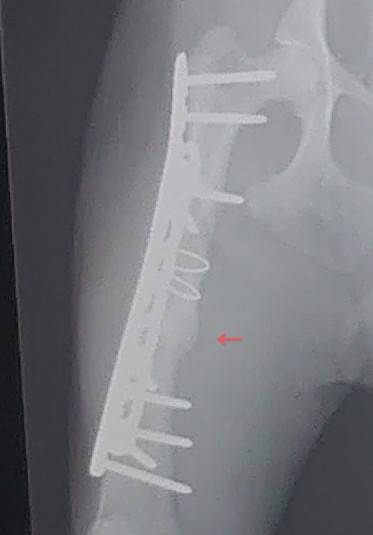

9月初旬、クルくんの預かりさんに定期検診に行って頂きました。獣医さんがおっしゃるには、もう少し時間のかかる部分もあるけれども、先月より骨が盛り上がってきていて、順調に骨が出来ているようです!少々走るのも、お散歩も長くても大丈夫です、差だけ注意してくださいと言われました。

おかげさまで順調な経過です!骨折は治療に時間がかかりますね。。でも、元気に過ごしているようで、私たちもとっても安心しました。またご報告させて頂きますね。